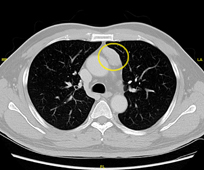

由於病情反覆且有惡化跡象,神經內科醫師安排王伯伯進行胸腔電腦斷層掃描 (Chest computed tomography)。檢查結果顯示,王伯伯的前縱隔腔 (anterior mediastinum) 存在一個直徑約五公分的腫瘤,懷疑是惡性的胸腺瘤 (thymoma)。考慮到王伯伯的病情和影像學檢查結果,神經內科醫師建議他轉診至胸腔外科,進一步評估進行根治性全胸腺切除手術的可行性。

圈圈標示處為前縱隔腔腫瘤 (胸腺瘤)